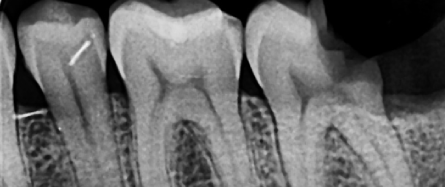

Clinical Examination

On examination, deep caries was noted on distal 37.

A periapical radiograph was taken, and treatment options were discussed. The patient agreed to undergo endodontic therapy for tooth 37.

Radiographic Examination :

Radiographs and clinical pictures during the treatment :

Treatment Procedure and Radiographic Documentation

Radiographs and clinical pictures were taken during treatment, including:

• Master cone GP periapical radiograph

• Post-operative X-ray